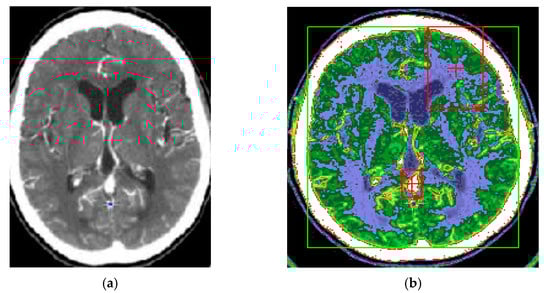

The proposed method for improving images with modified Wiener filter and nonlinear cellular network can be applied with success also with low contrast CT (computer tomograph) images. The improvement of tomographic image quality aims at obtaining superior visibility of the image components, the adaptive increase of the contrast, in order to be interpreted as easily as possible by the specialist doctor. Figure 7, Figure 8 and Figure 9 show the results obtained in the case of such images.

The interest in such filters is determined by the fact that much of the existing information in the images is provided by contours, and most of the noise removal methods cause them to fade. In the present case, at the cost of removing a smaller amount of noise in the contour-containing regions, it can be better preserved, as shown by the results shown in Figure 7, Figure 8 and Figure 9. There is thus a trade-off between the amount of noise removed and the quality of preserving the contours in the image.

It should be noted that in the results presented in Figure 8 and Figure 9, the noise reduction is accompanied by an improvement of the contours of the processed image, leading to a microscopic analysis, highlighting very well the contours of tumor formations from diseased tissues to healthy tissues. Such an estimate is useful for the medical act, especially for surgery. Additionally, the proposed method, in addition to the contour enhancement property, highlights the deconvolution applications for removing or reducing the blurring of energy areas in images by highlighting their vascularization elements (Figure 8 and Figure 9).

Imaging techniques are especially useful for interpreting biomedical CT/MRI images. The improvement of the quality of the tomographic images aims at obtaining a superior visibility of the image components, the adaptive increase of the contrast, to be interpreted as easily as possible by the specialist doctor. In the case of CT images, when the contrast is satisfactory ( λ = 0.05 ) , it is necessary to preprocess the image using the Wiener filter proposed in the article and nonlinear cellular network. Thus, image analysis after edge detection in preprocessed images can be facilitated. Based on the presented results, the validity of the proposed method for improvement of medical images can be found by the simultaneous use of the modified Wiener filter described in the article and cellular neural networks, for concrete applications in CT medical imaging.

Figure 8. (a) Initial image with low contrast; (b) improved image—CT cranial layer image processed with modified Wiener filter; (c) CT cranial layer image processed with the combined algorithm between the modified Wiener filter and the nonlinear cellular network.